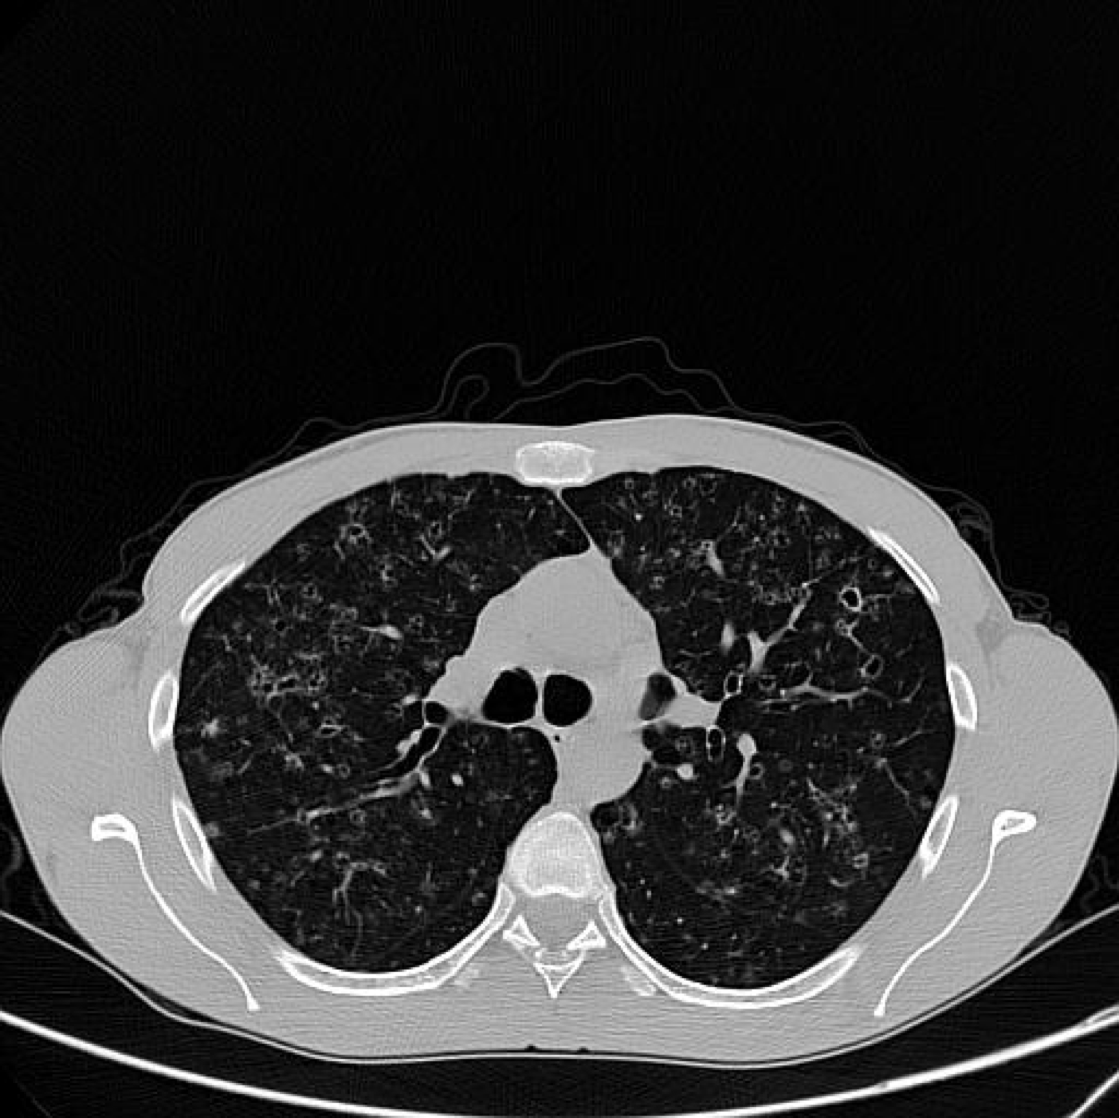

A 64-year-old woman was admitted to our hospital with a 10-days history of sore throat, fever and a 3-days history of painful left neck mass. She had been treated with Cefixime, owing to complains of sore throat and fever at another primary clinic. Her throat examination showed mild erythema. A painful neck mass on the left side was observed. Laboratory findings were as follows: white blood cell count, 11,220/L; and C-reactive protein, 16.9 mg/dL. No organism was isolated from blood culture. Enhanced cervical computed tomography (CT) revealed enlargement of the left internal jugular vein, in which hypodense lesions compatible with thrombosis could be seen. High-resolution chest CT revealed patchy opacities compatible with pulmonary septic emboli. Although septicemia was not demonstrated in blood culture, probably because she was already taking antibiotics, the patient was diagnosed with Lemierre’s syndrome.